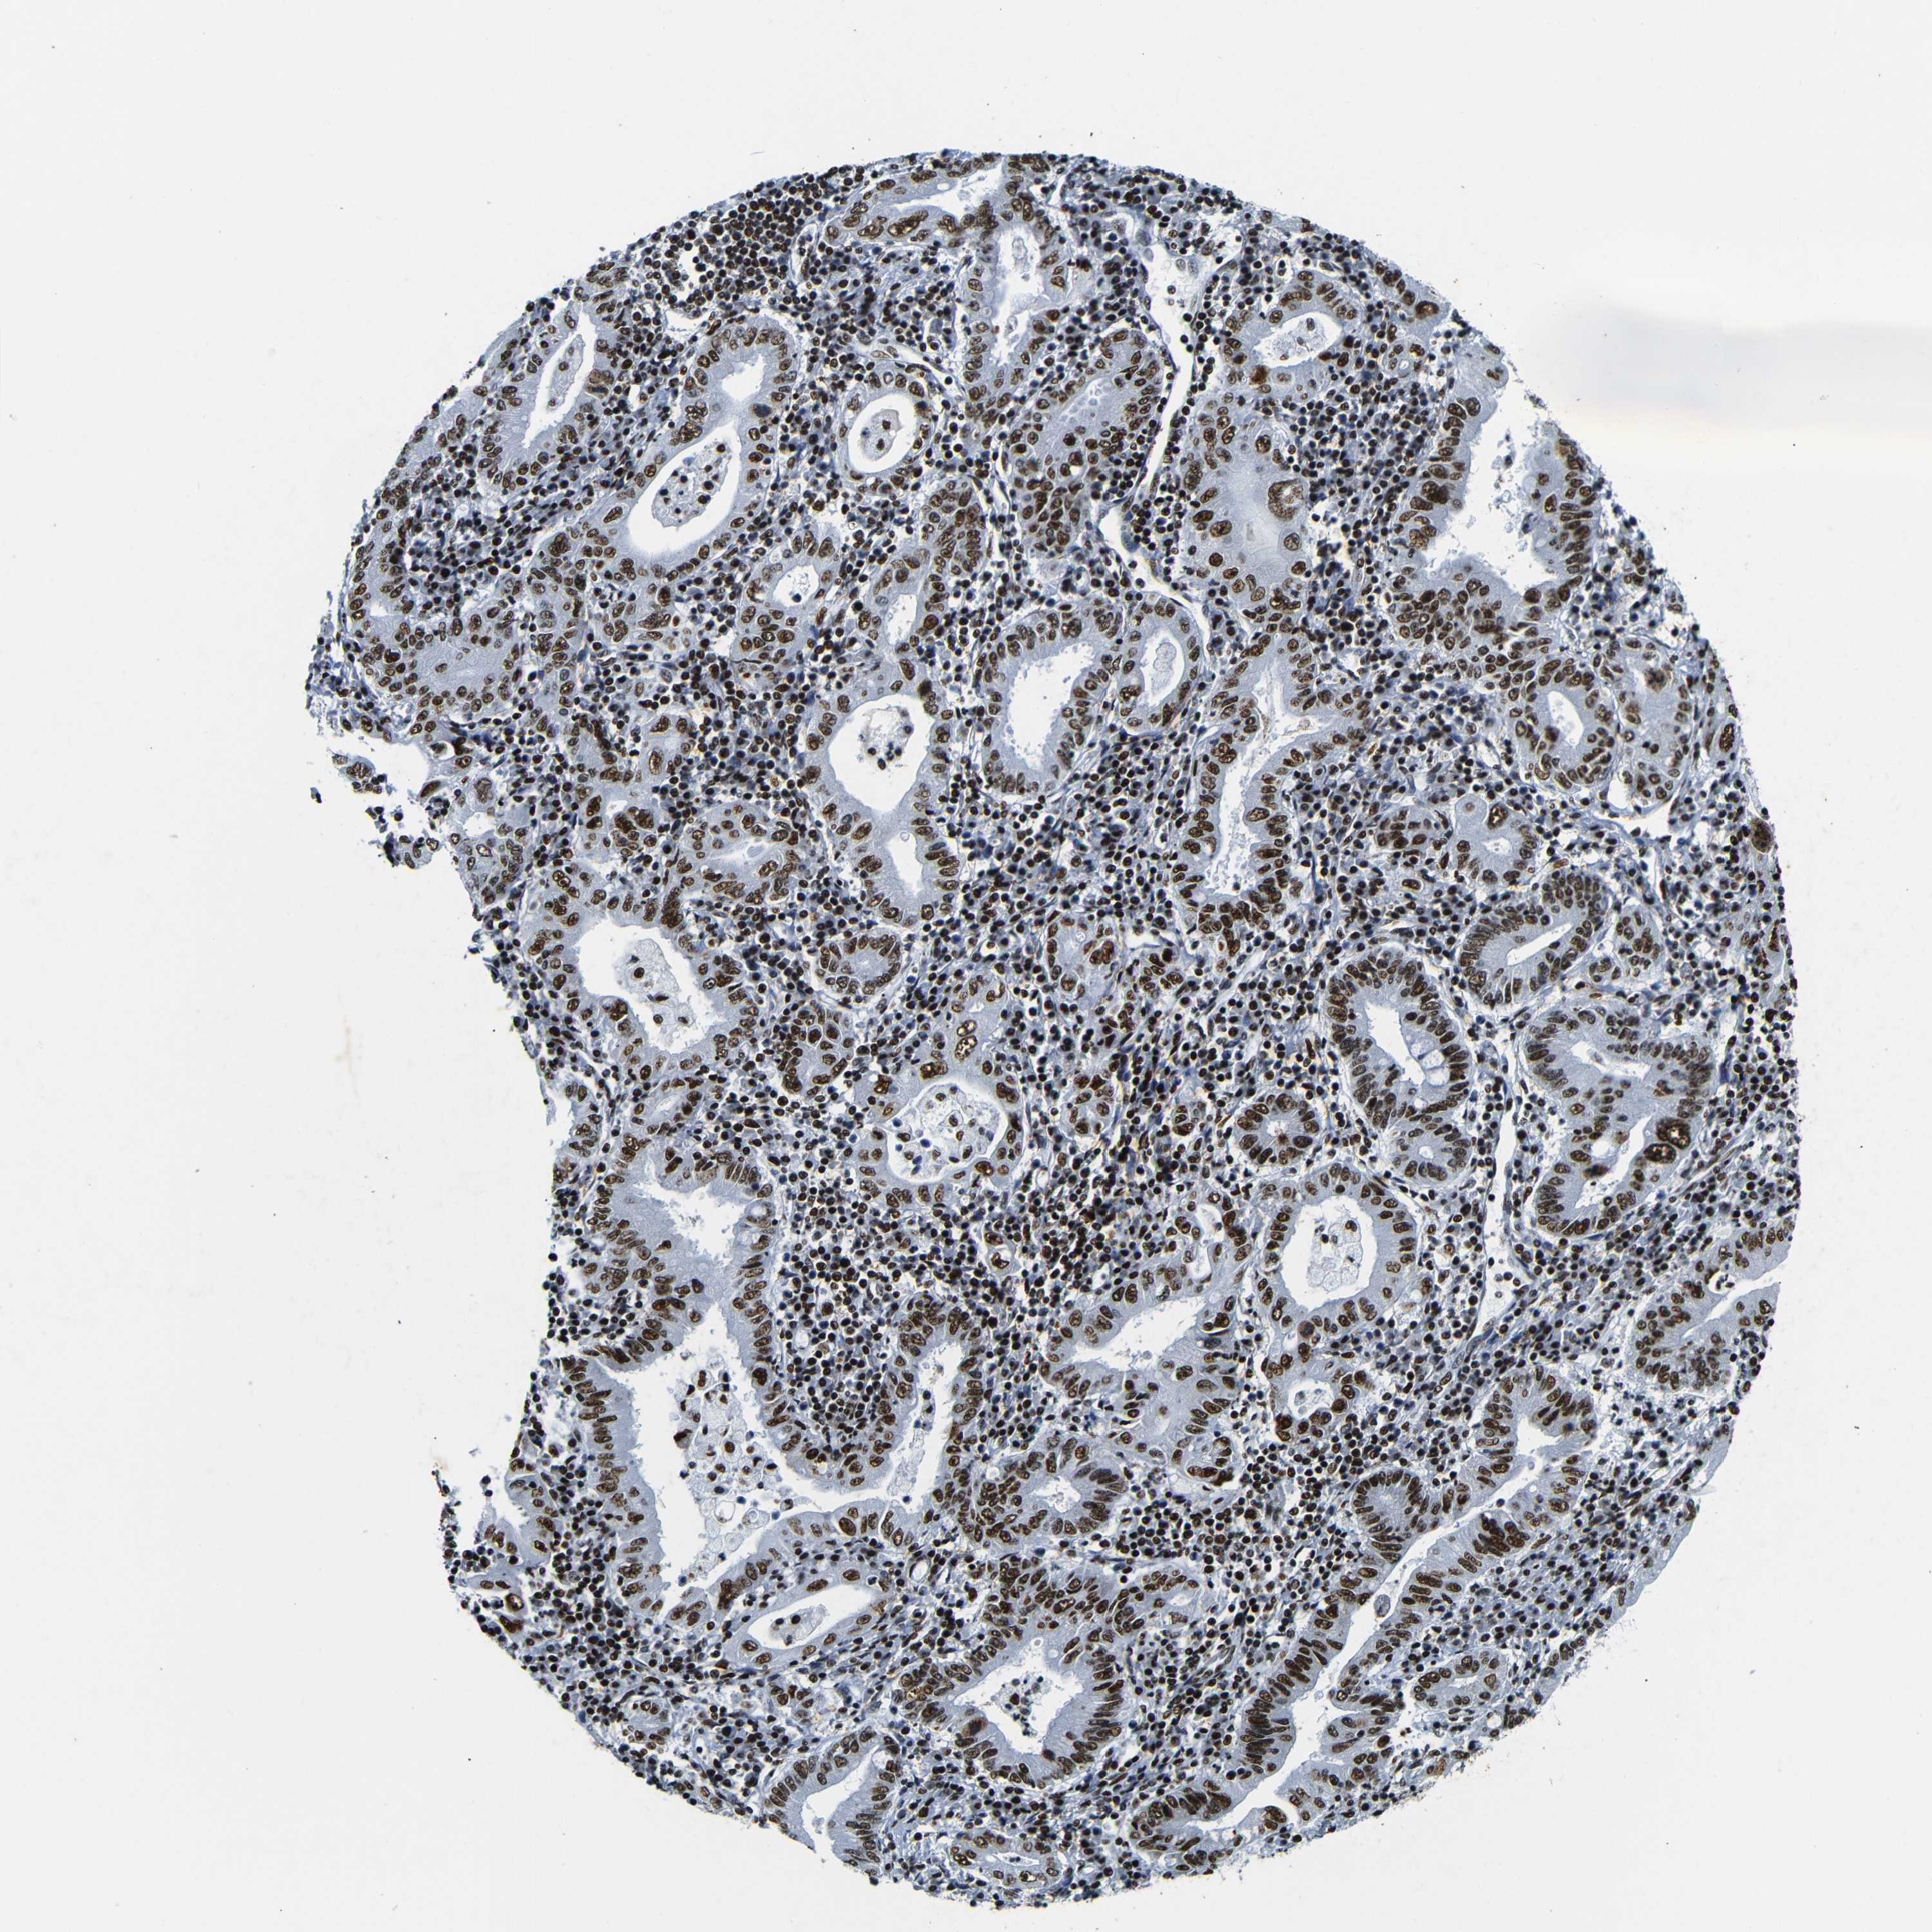

STOMACH CANCER - Protein expressioni

A mouse-over function shows sample information and annotation data. Click on an image to view it in a full screen mode. Samples can be filtered based on level of antibody staining by selecting one or several of the following categories: high, medium, low and not detected. The assay and annotation is described here.

Antibody stainingi

Antibody staining in the annotated cell types in the current human tissue is reported as not detected, low, medium, or high, based on conventional immunohistochemistry profiling in selected tissues. This score is based on the combination of the staining intensity and fraction of stained cells.

Each image is clickable and will lead to virtual microscopy that enables deeper exploration of all samples and also displays staining intensity scores, fraction scores and subcellular localization as well as patient and tissue information for each sample.

Antibody HPA061301

Antibody CAB013073

Staining

High

Medium

Low

Not detected

Intensity

Strong

Moderate

Weak

Negative

Quantity

>75%

75%-25%

<25%

None

Location

Nuclear

Cytoplasmic/membranous

Cytoplasmic/membranous,nuclear

Adenocarcinoma, NOS

Adenocarcinoma, High grade